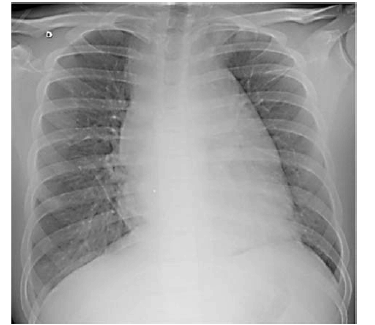

Paciente do sexo masculino, de 16 anos de idade, estudante, compareceu a consulta no posto de saúde, acompanhado da mãe, com queixa de dor no peito. Relatou início dos sintomas após colisão quando jogava futebol. O exame físico foi normal. A imagem a seguir mostra o Raio X do paciente, solicitado por insistência da mãe.